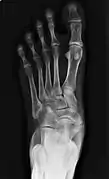

Radiological images

Cornuate navicular bone